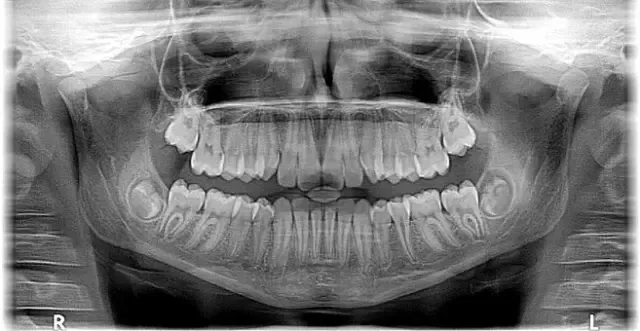

- odstranjevanje mehkih in trdih zobnih oblog

Z vsemi naštetimi postopki poskrbimo za zmanjšanje krvavenja dlesni in preprečujemo razvoj parodontoze.

Peskanje se izvaja s posebnim prahom pod pritiskom. Je varno in neboleče. Izvaja ga ustni higienik ali zobozdravnik. Po peskanju sledi poliranje zob, s čimer zgladimo zobne površine.